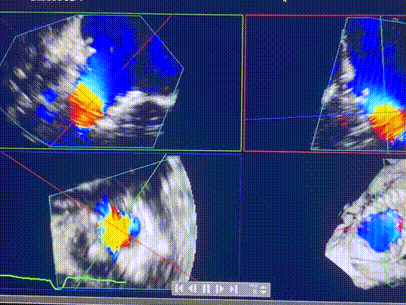

術(shù)前超聲提示重度三尖瓣反流

接受本次LuX-Valve Plus治療的是一位三尖瓣重度反流的高齡女性,患者早前曾由于二尖瓣疾病行經(jīng)導(dǎo)管二尖瓣置換術(shù),植入Tendyne瓣膜一枚,且有ICD植入史。術(shù)前CT分析結(jié)果顯示,瓣環(huán)大小為47.6mm,血管無明顯迂曲和鈣化。由于患者三尖瓣解剖結(jié)構(gòu)復(fù)雜,二尖瓣位人工瓣膜造成的超聲偽影和ICD導(dǎo)線的干擾使得歐洲沒有其他合適的商業(yè)化和臨床試驗的產(chǎn)品可以對其進行治療。經(jīng)過Rodrigo Estévez-Loureiro教授團隊的詳盡術(shù)前評估,認為LuX-Valve Plus經(jīng)導(dǎo)管三尖瓣置換系統(tǒng)可以對該患者進行有效的治療。因此,Rodrigo Estévez-Loureiro教授團隊最終決定使用這一中國創(chuàng)新器械為患者進行手術(shù)。法國波爾多里爾大學(xué)附屬醫(yī)院的Thomas Modine教授與加拿大圣保羅醫(yī)院的Anson Cheung教授全程線下指導(dǎo)本次手術(shù)。